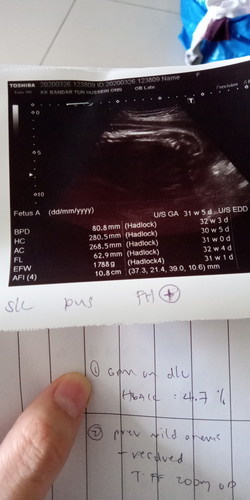

air ketuban makin berkurang

26/3/2020 scan. previous check up hb tetiba drop. tapi masa scan ni alhamdulillah hb kembali normal. tapi MO detect air ketuban (afi) makin sikit. so kena monitor gerak baby dan kalau ada cecair keluar. risau sbb anak 2nd prem baby. lahir 33w5d disebabkan leaking 5hari. untuk 4th baby ni harap keluar macam abg dan kakak ketiga dia lah. dekat dekat due. jgn awal sgt. siapa geng due bulan 5? saya 20/5/2020 ??